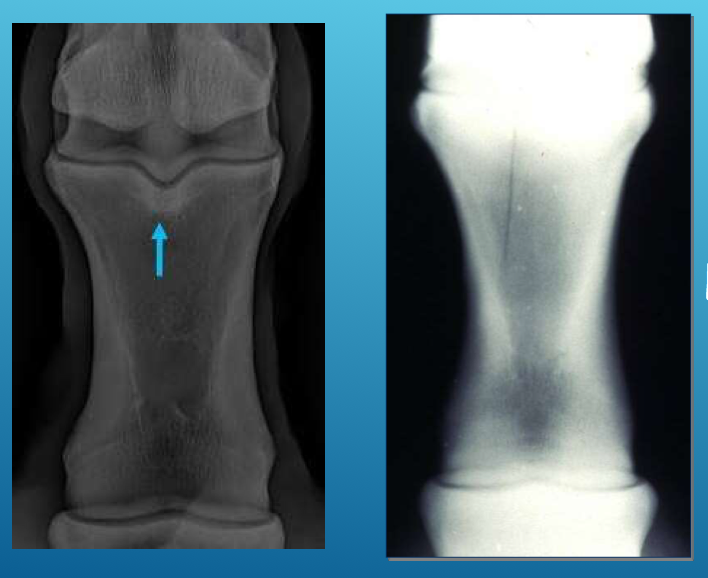

This injury on the 3rd metacarpus is most commonly seen in which patient

2 yr old race horse in training

(Image is of a bucked shin)

How do you reduce the incidence of bucked shins?

regular short distance breezing and less long distance galloping

T/F: Osteostixis is recommended for unicortical fractures of the splint bone

False

Osteostixis is recommended for unicortical fractures of the cannon bone